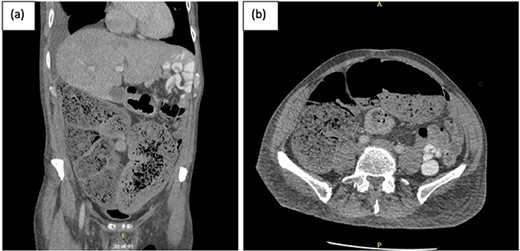

A subsequent gastrograffin study was performed the next day with persistent contrast in nondilated small bowel at 8 hours and nil therapeutic clinical improvement (Fig. 3).

Gastrograffin study demonstrating markedly dilated gas filled loop of large bowel seen extending from the pelvis into the right upper quadrant, consistent with a dilated loop of redundant sigmoid, with no obvious contrast in the colon but some contrast in the small bowel loops in the left upper quadrant.